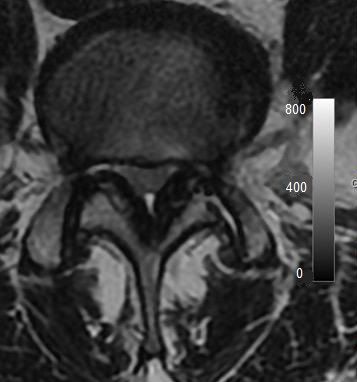

The diagnosis of LSS was then confirmed with imaging studies, either CT or MRI (Fig. 1). Dynamic myelography was useful to search for any compression not detected on the static images.